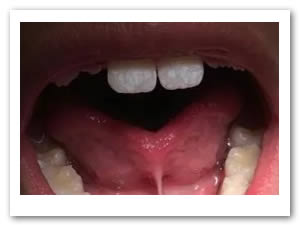

• Se realizó prueba para ratificar la proyección lingual la cual fue exitosa (Figura 10).

Figura 10. Prueba exitosa de tracción lingual

ANTES

DESPUES

La anquiloglosia es una patología congénita bucal que debe ser diagnosticada y remitida para su tratamiento temprano. Esta es asintomática y es detectada por la exploración del movimiento lingual. El manejo quirúrgico proporciona beneficios para la posterior terapia del lenguaje y para el desarrollo normal de las estructuras orales, principalmente de la mandíbula. (Chaubal & Baburaj, 2011) Existen muchas técnicas para realizar este procedimiento pero se debe elegir la más adecuada para el manejo de cada caso en particular. (Azevedo et al ., 2014) En el presente caso se realizó la escisión  quirúrgica del frenillo para permitirle una correcta movilidad a la lengua y una genioplastía para evitar la reinserción de las fibras del frenillo. Se empleó una técnica convencional con anestesia local la cual fue bien tolerada por el paciente debido a la corta duración de la cirugía. Los resultados obtenidos fueron muy satisfactorios y el paciente fue remitido a la clínica de ortodoncia de dicha institución; también se les dieron indicaciones a los padres para que lo llevaran con un logopeda y con un psicólogo para sus respectivas terapias.

Existen varias técnicas quirúrgicas para tratar la anquiloglosia, la edad ideal para realizar el tratamiento es en el período de lactancia del bebé o al inicio de la edad escolar concomitante con el aprendizaje del idioma; apegado a esto podemos evitar alteraciones en la fonación, deglución, anomalías de posición dental y problemas en el desarrollo y crecimiento de los maxilares. La técnica propuesta fue segura, efectiva y se logró la meta del tratamiento quirúrgico. El paciente se mostró satisfecho y podía mover la lengua libremente dejándolo listo para su segunda fase de tratamiento con ortodoncia interceptiva.